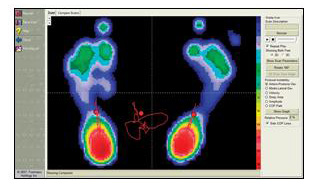

Click on the Button below for information on our new state of the art orthotic technology by Footmaxx.